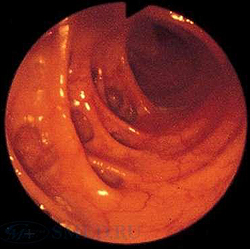

(а) На рентгенограмме ободочной кишки визуализируются утолщенные складки, наличие которых обусловлено утолщением циркулярной мышцы (стрелки) — вторичные изменения по отношению к укорочению и утолщению продольной ленты ободочной кишки. Дивертикулы (указатели) представляют собой мешковидные выпячивания стенки кишки между волокнами циркулярного мышечного слоя.

(в, г) На фотографиях, выполненных при колоноскопии, визуализируются множественные входные отверстия дивертикулов (указатели). Дивертикулы часто могут заполняться уплотненными каловыми массами и плохо опустошаются. Дивертикулиты: типичные КТ и УЗ-признаки.

(Справа) На рентгенограмме, выполненной при ирригоскопии с двойным контрастированием, определяется дисторсия просвета ободочной кишки. Выбухающие участки В представляют собой дивертикулы, в то время как неравномерно распределенные вдавления стенки В отражают изменения, обусловленные гипертрофией циркулярного мышечного слоя.